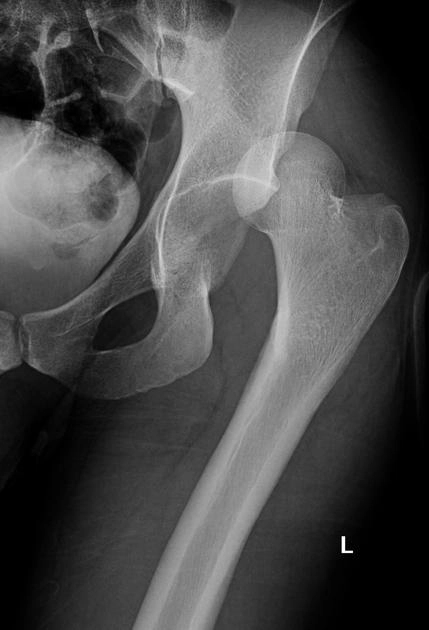

Hội chứng kẹt (chẹn) xương đùi-ổ cối (Femoroacetabular Impingement - FAI)